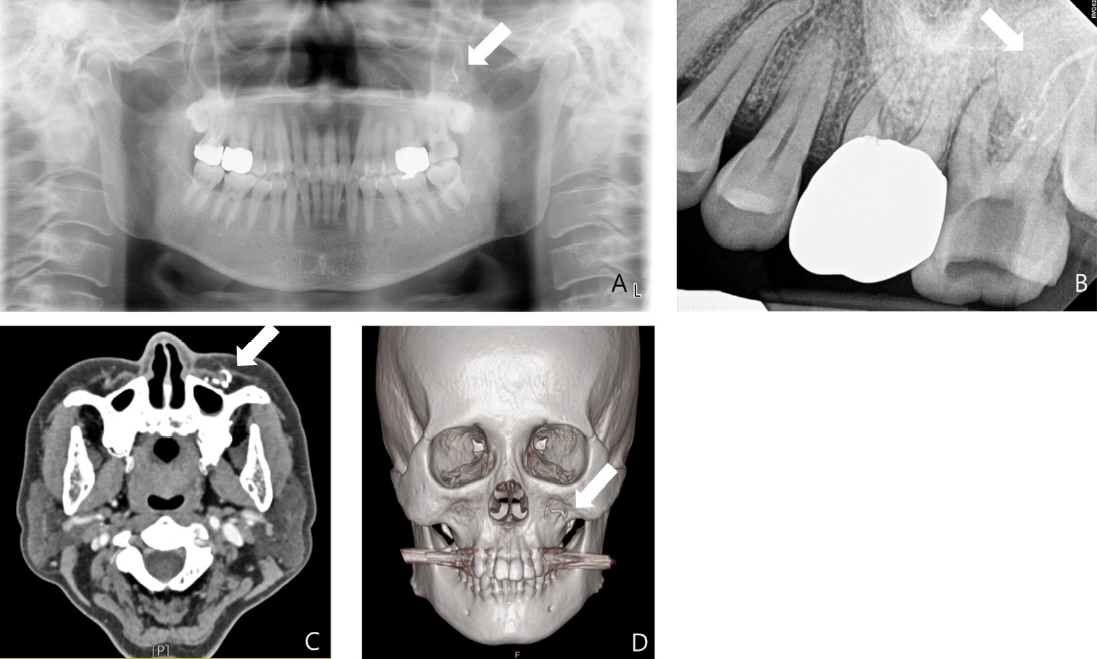

Panoramic view, periapical view and enhanced computed tomography (CT) scan were performed to evaluate the condition further, revealing the extrusion of calcium hydroxide paste over the root apex (Figs. 2A and B). Facial angio CT performed upon presentation to the emergency department showed opacification loss in the branches of the left maxillary artery and skin loss with depression in the left buccal area, without evidence of a fistula tract or subcutaneous inflammation, indicating a possible vascular cause. Based on the findings from the enhanced CT scan, the patient was diagnosed with Nicolau syndrome (Figs. 2C and D).

Radiographic examination performed at the initial examination. A and B. Periapical and panoramic views show extrusion of calcium hydroxide paste beyond the root apex of the left maxillary second molar (arrows). C and D. Facial angio computed tomography demonstrate loss of contrast in the posterior superior alveolar artery, indicating arterial obstruction (arrows).

A. Panoramic radiograph taken approximately six weeks after the incident shows persistent radiopaque material in the periapical region, consistent with extruded calcium hydroxide. B. Coronal cone-beam computed tomogrpahic image demonstrates the presence of extruded calcium hydroxide within the adjacent soft tissue space.